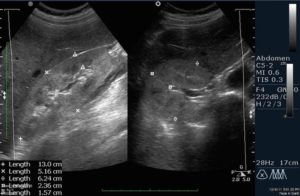

Диффузные изменения в почках диагностируются с помощью ультразвука. С точки зрения данного метода патологию подразделяют на четкие, нечеткие, умеренные, слабые и выраженные изменения.

На ультразвуковом аппарате можно наблюдать признаки потемнений и нечеткости контуров, анаэхогенные участки в паренхиме, зоны гипреэхогенности и анаэхогенности в ЧЛС, а также изменения контуров лоханок и капсулы почки.

При проведении УЗИ диффузные изменения проявляются асимметрией расположения, неравномерностью толщины, деформациями мозгового участка, неровными контурами органа и другими отклонениями структуры. Выявление этих особенностей структуры почек в некоторых случаях позволяет определить возможную причину их появления и назначить адекватное лечение.

Наиболее востребованным считается ультразвук ввиду доступности, отсутствия сложных подготовительных процедур, информативности при низкой цене. Эхо-признаками наличия диффузно-деструктивного поражения ЧЛС или синусов являются:

- утолщение в виде затемнения почечной ткани;

- подача эхо-сигнала от почечных синусов;

- ослабление эхогенности;

- неясные очертания паренхиматозной ткани;

- истончение синуса;

- выявление признаков наличия жидкости в лоханке;

- усиление насыщенности почечных тканей сосудами;

- проблемы с кровоснабжением органа;

- затемнение в почечной вене, что характерно для тромбоза;

- проблемность определения эхо-структур;

- обратный кровоток в почечных артериях;

- невозможность определения почечных вен.